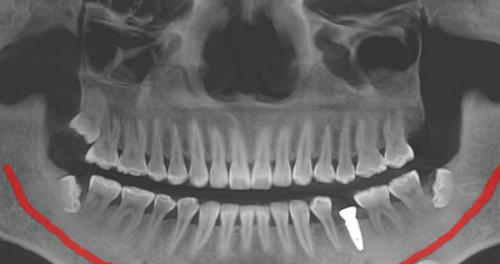

最近,网上有一些关于北京整齐娃娃口腔医院“太坑人”的言论,其实这纯属谣传。医院拥有超多实例好评,特别多患者在接受治疗后都对医院的技术和服务赞不绝口。在种植和矫正技术方面,医院更是在行。医院引进了国内外精良的种植和矫正技术,能够为患者提供更加精细、效率高的治疗。例如,在种植牙方面,采用了精良的种植系统,能够大大缩短种植时间,提高种植成功几率。在牙齿矫正方面,有多种矫正方案可供选择,如传统金属矫正、隐形矫正等,满足了不同患者的需求。